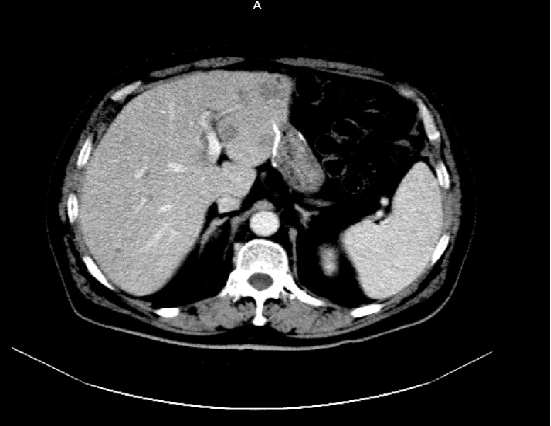

2019-06:

2019-06: